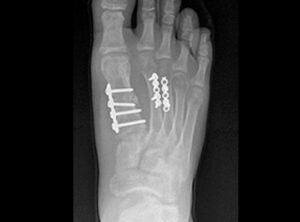

Hallux valgus

El hallux valgus es una deformidad del pie caracterizada por la desviación medial del 1r metatarsiano y la desviación del dedo gordo del pie (hallux) lateralmente. A menudo es causada por la enfermedad articular degenerativa o por la presión del calzado.

Con mayor frecuencia en las hembras, el hallux valgus hace que el 1er metatarsiano cambie de lugar medialmente y los huesos sesamoideo se desplacen lateralmente. Esto resulta en los huesos sesamoideo que yacen entre las cabezas de los metatarsianos 1 y 2.

Cuando los tejidos circundantes se hinchan, una Bursa subcutánea se puede formar. Cuando esta Bursa está inflamada esto puede causar un gran dolor en el pie. Una deformidad dolorosa del hallux valgus se refiere como juanete.